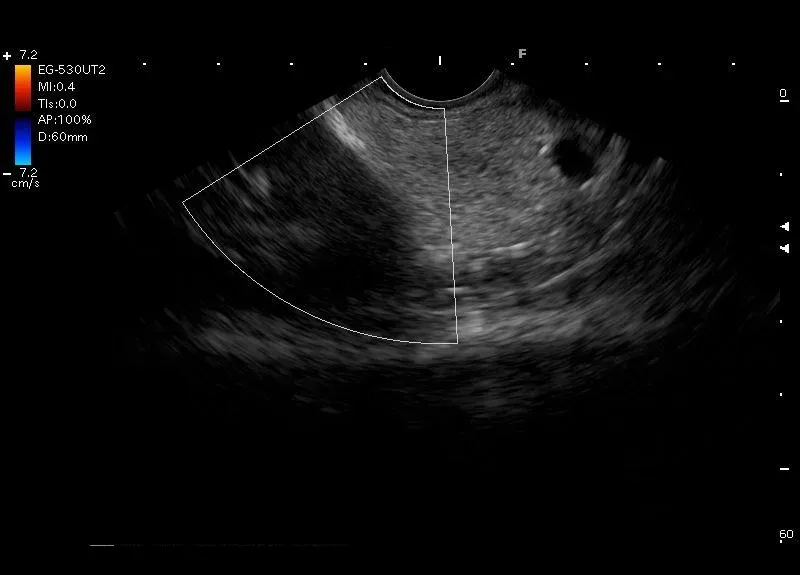

Ogon trzustki zobrazowany przez głowice EUS przyłożoną w trzonie żołądka .Widoczne są także fragment nerki i śledziony.